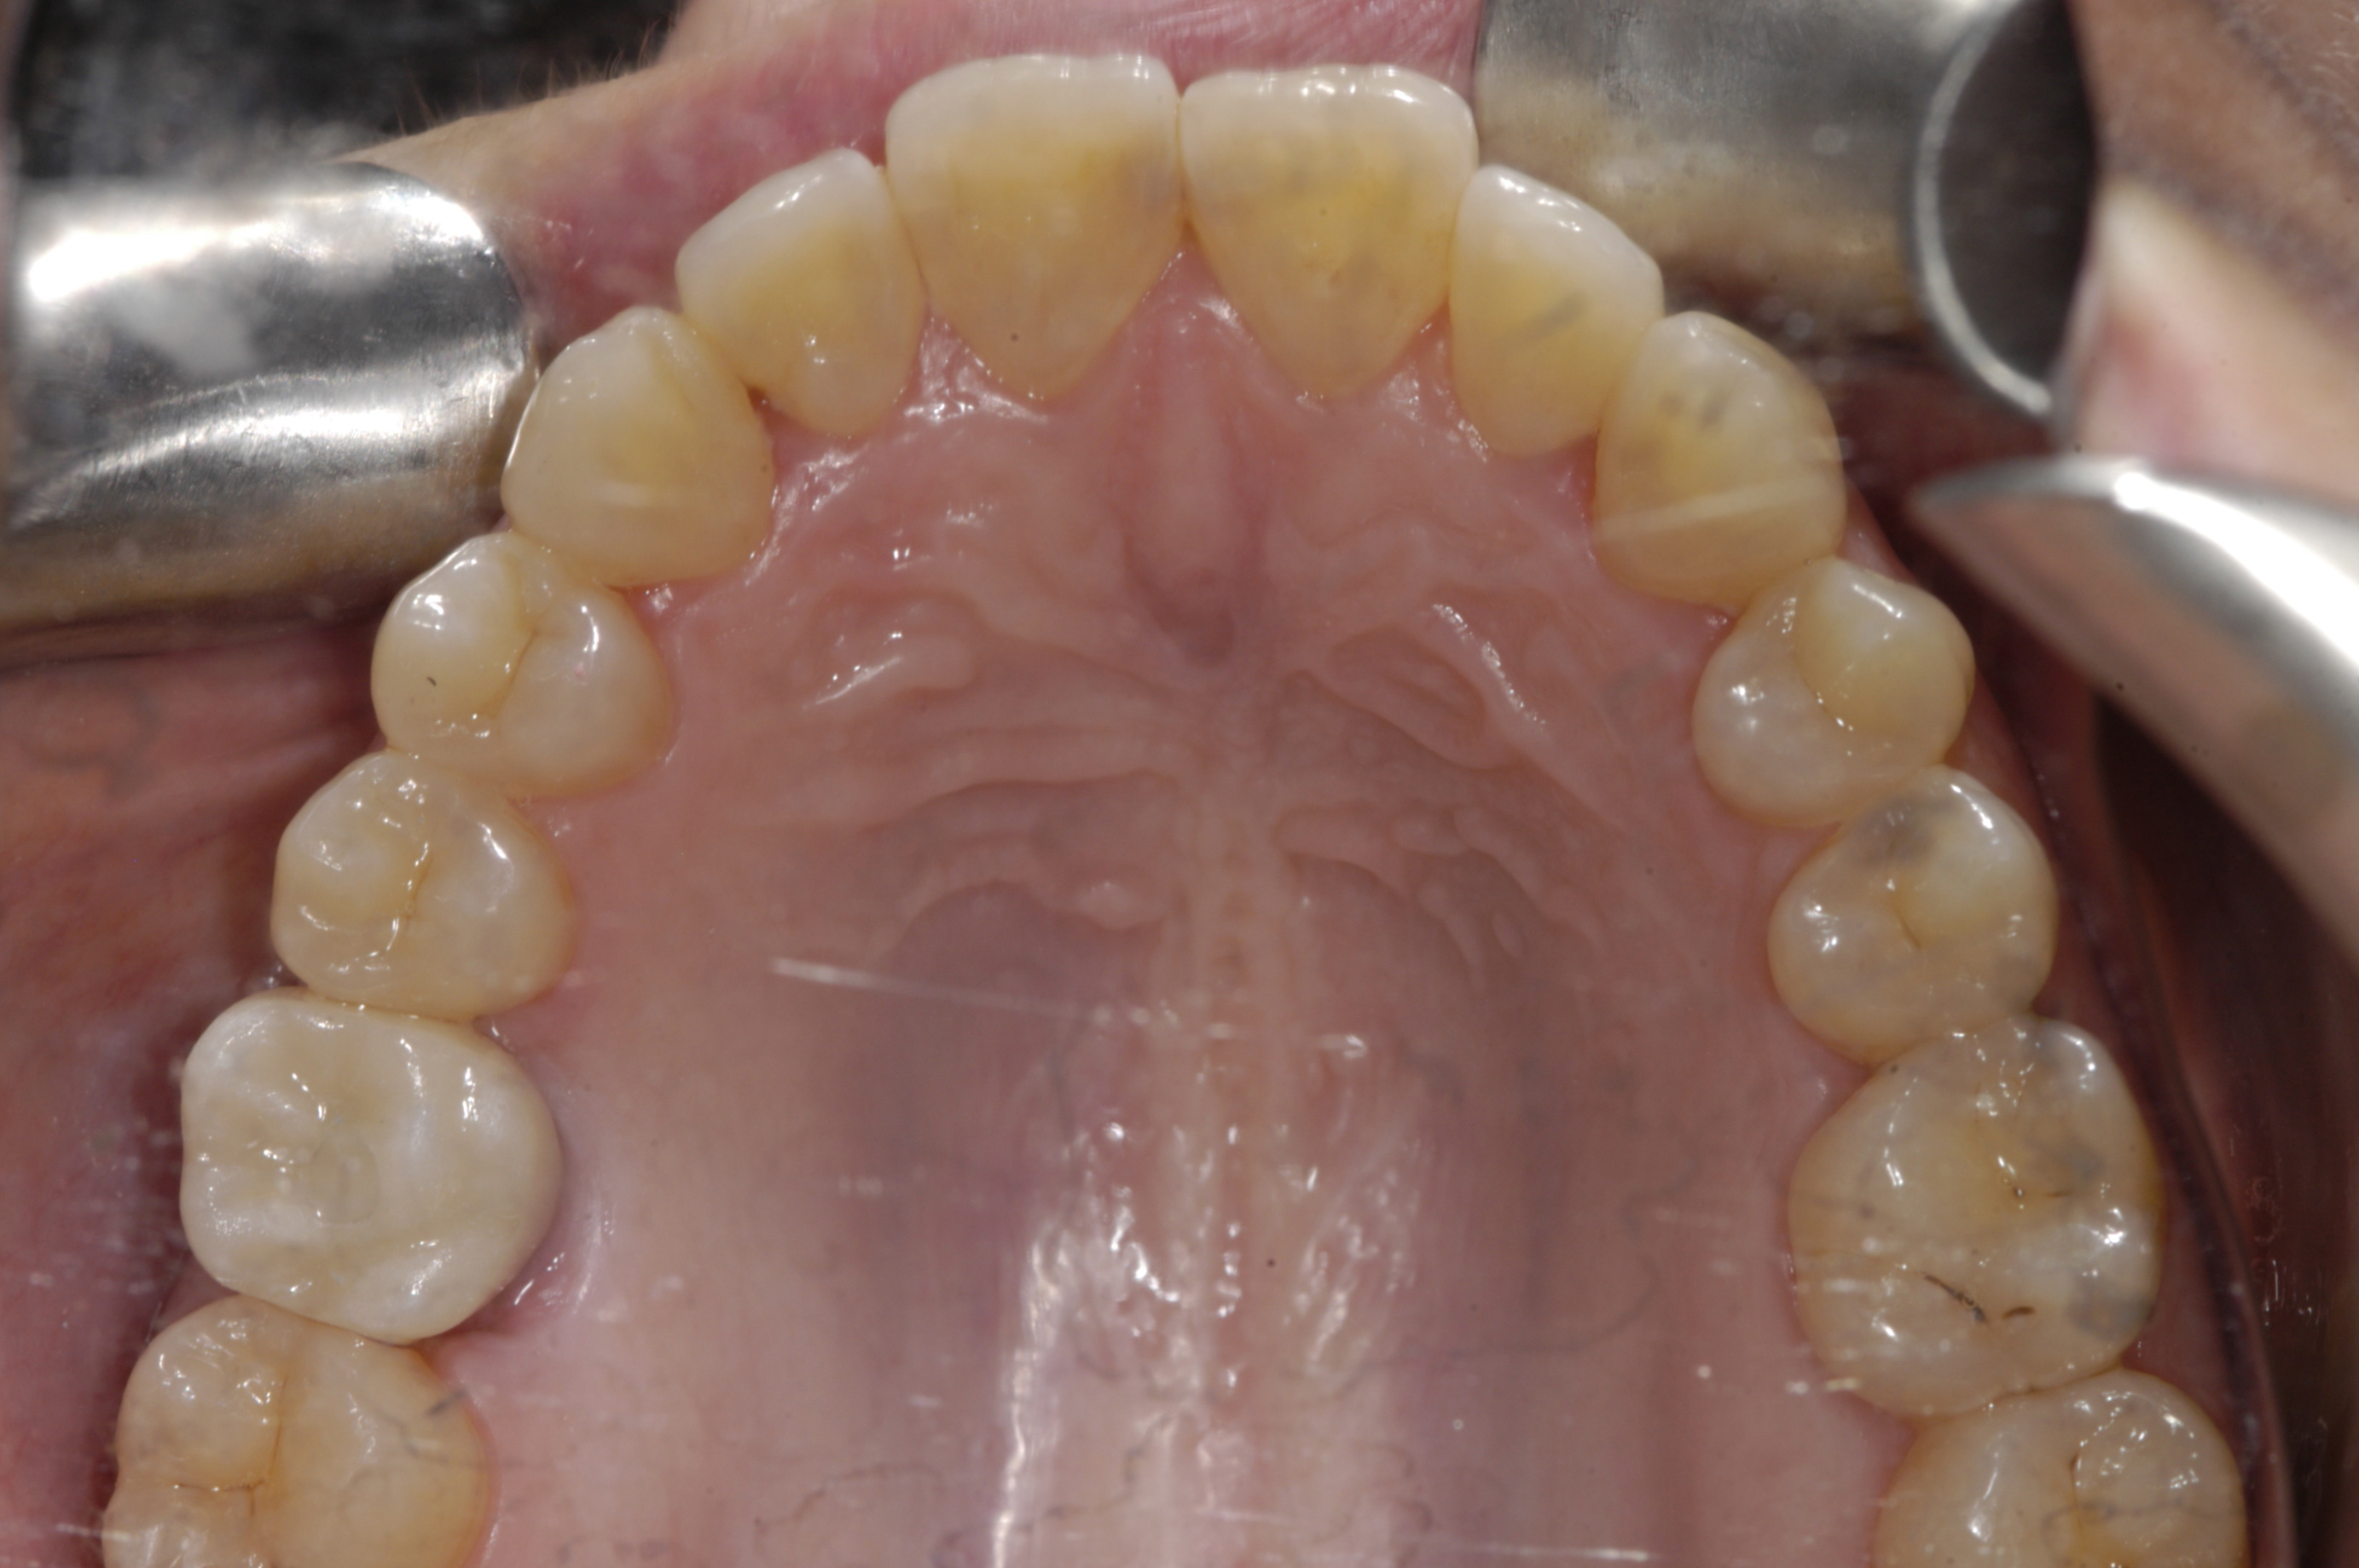

The first appointment is diagnostic. The patient’s medical and dental histories are reviewed and a CBCT is exposed, or arranged for if a scanner is not on site. Accurate study models are obtained, and a clinical examination is conducted, particularly looking for signs and symptoms of occlusal disease. A periodontal exam is also completed. If occlusal13,14 or periodontal disease is present, it should be treated before starting implant therapy.

Before completing the clinical exam, the edentulous site is evaluated for adequate volume in facial-lingual and mesial-distal dimensions. The smallest standard implants are 3.0 mm in diameter, but their restorative platform is 3.5 mm, andshould be 1.5 mm from adjacent teeth,15 requiring a minimum mesial-distal dimension of 6.5 mm (3.5 mm + 1.5 mm + 1.5 mm). Accounting for 1 mm of bone facially and lingually,15 plus approximately 1.5 mm of gingiva over each, requires a minimum facial-lingual dimension of 8 mm (3 mm + 1 mm + 1 mm + 1.5 mm + 1.5 mm). The ridge should also be palpated for facial undercuts commonly found apical to the muco-gingival line. These undercuts can affect the position and angulation of implants and should be further evaluated with CBCT.

Finally, the amount of attached gingiva is evaluated. There is disagreement regarding the need for attached gingiva around implants,16,17 but the generally accepted minimum is 2 mm.18,19 A zone of 3 mm is recommended by this protocol for esthetics. A simple method of evaluation is to place a periodontal probe against the cementoenamel junctions of the adjacent teeth. At the midpoint between the adjacent teeth, the buccal aspect of the implant should exit 2 mm lingual to the probe. Therefore, if attached gingiva extends 1 mm facial to the probe, there should be adequate keratinized tissue. If the minimum requirements of bone volume and attached gingiva are not met, ridge augmentation and/or soft-tissue grafting are needed prior to implant placement. If the minimum requirements are met, digital impressions of both arches are obtained before dismissing the patient.